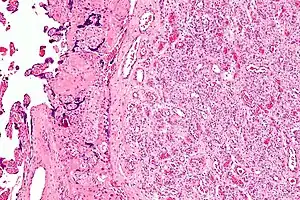

| Micrograph of a chorangioma. H&E stain. | |